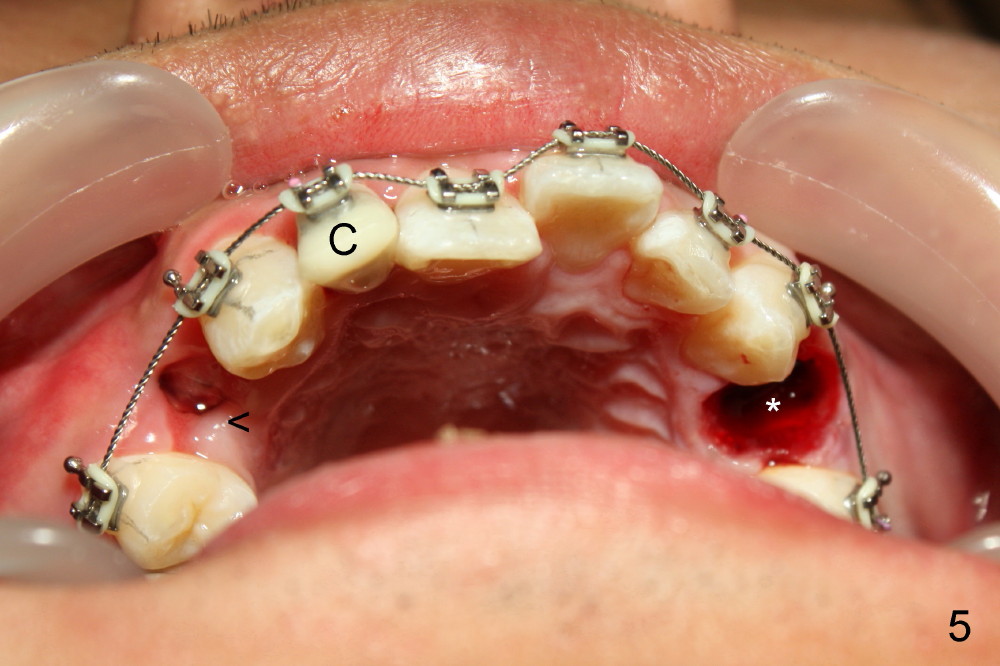

A 21-year-old man has severe maxillary protrusion (Class II malocclusion) with crown fracture of #7 (Fig.1,2,3 (latter two mirror images). Treatment plan is to place pre-fabricated post and provisional for #7 (Fig.4,5 C) and start ortho treatment with extraction of upper 1st bicuspids (Fig.5 *, <). When ortho finishes, fabricate full-coverage porcelain crown for #7.

The 1st step of ortho is arch wire sequence to align the arches (from thin round wires to thick rectangular ones). The 2nd is to retract the canines distal (Fig.1 (planning), Fig.7 (6 months post bracketing), Fig.8 (7 months), using closed coil springs (*). The 3rd step is to move the remaining anteriors together distal using posted wire (^) and again closed coil springs (Fig.9; 8 month into treatment). Note the overjet between upper and lower anteriors (Fig.9: *). This space allows the upper incisors to move backward.